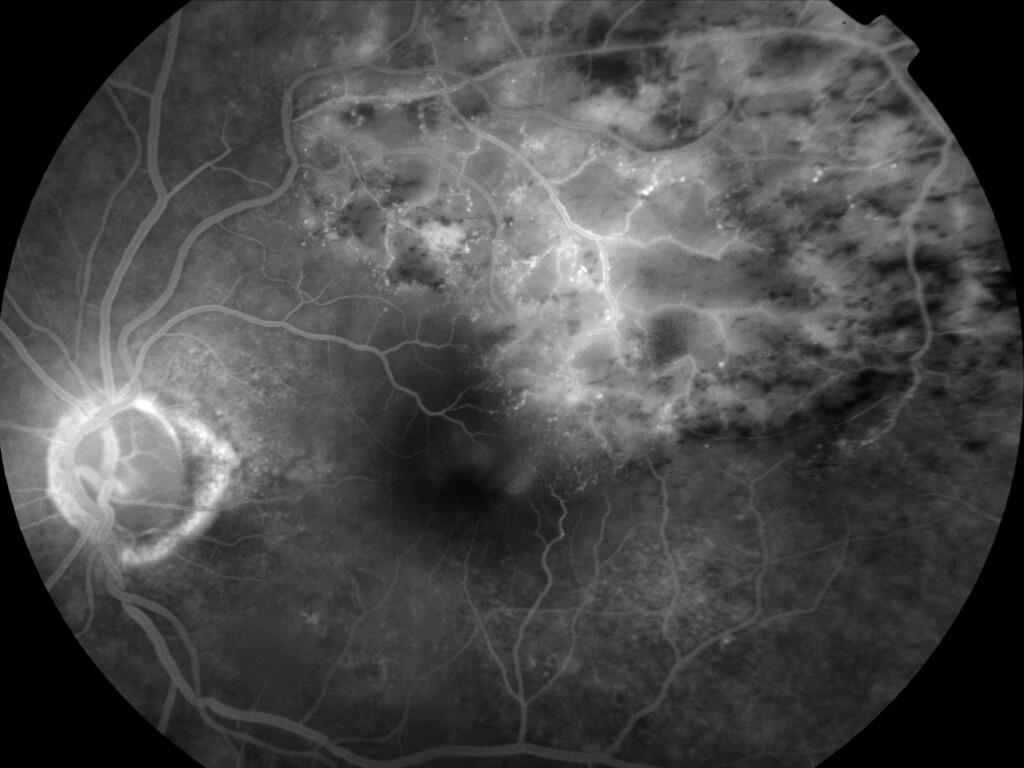

OCCLUSION DE BRANCHE DE LA VTS DE FORME ISCHEMIQUE MAJEURE